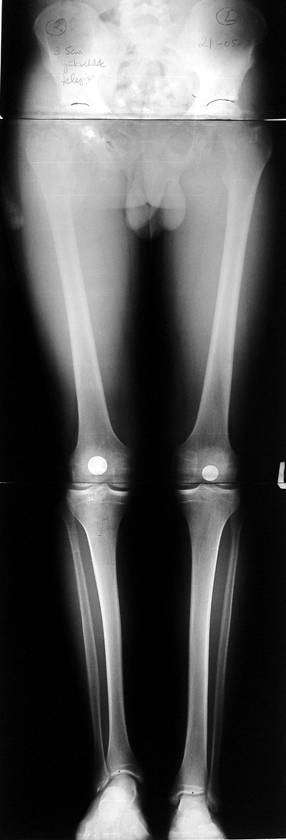

Many patients don’t want to use a shoe support thicker than 2 cm. For length differences between 2 cm and 5 cm, shortening may be considered for tall patients. This can be performed in growing children with a small, minimally invasive, uncomplicated procedure called epiphysiodesis. This means surgical disruption of one or more growth plates. There is a growth plate at the ends of femur, tibia and fibula; this procedure does not halt all growing of the leg. The growing of the longer leg is calculated and halted to allow the shorter leg to catch up.If the procedure is performed at a too early or too late age, the correction may be too much or too little, respectively. Hence, it is important to accurately calculate the most appropriate age for epiphysiodesis. When and at which bone segment epiphysiodesis will be performed shall be calculated by the doctor using different methods such as Gren-Anderson diagram, Moseley curve or Paley’s multiplier method.Epiphysiodesis is not an option for adults because growth plates ar closed. In adults, a bone segment has to be excised surgically in order to shorten the leg. This is usually performed at femur and bone is later fixed with an intramedullary nail. The biggest advantage of this system is that it acutely provides limb length equality for discrepancies less than 5 cm. The common disadvantage of epiphysiodesis and shortening is the shortening of total height of the patient. Because we don’t advice shortening more than 5 cm, height loss can’t be more than 5 cm. For patients who don’t want an epiphysiodesis or shortening operation for length inequalities less than 5 cm, limb lengthening can be preferred in order to equalize the length difference.This can be combined with epiphysiodesis and shortening to decrease a need for another lengthening operation or to decrease the lengthening amount required.